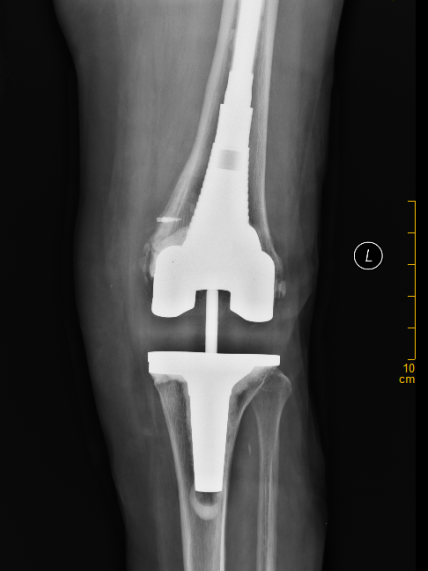

经详细查体,发现陈女士左膝关节肿胀明显、内翻畸形,关节脱位,无法行走,X线片显示,假体松动,内侧股骨髁、内侧胫骨平台部分骨溶解,左下肢内翻畸形,确诊为“左侧人工膝关节置换术后假体松动”并收住晋江市医院骨科。

▲ X线提示:假体松动,内侧股骨髁、

内侧胫骨平台部分骨溶解,左下肢内翻畸形

▲ 术后X线提示:关节位置良好,关节关系正常